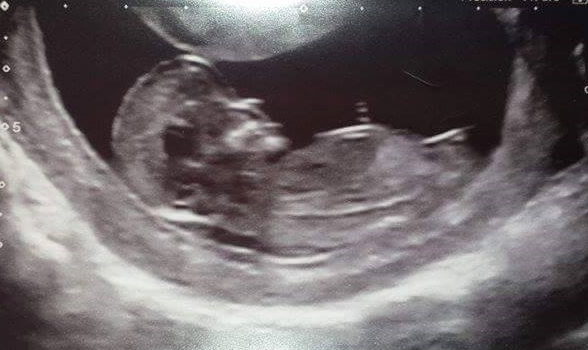

This is my 12 week scan photo.

based on the nub theory i am guessing a little girl but who knows.

we find out on 30th october and i cant wait! just hope baby plays ball. I see no shame in finding out at 20 weeks. its a surprise no matter what. im just to impatient. dp still doesn't want to find out though.